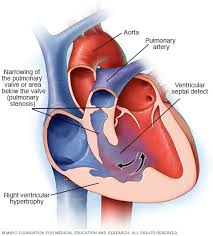

Overview

Package includes:

Days in hospital : 10 to 11 Days (For patient and one attendant)

Days in hotel : 14 Days (For patient and one attendant)

Room type in hospital : Shared

Room type in hotel : Private

Hotel category: Standard

Value added benefits of the TOF treatment:

Ø Doctor consultation charges

Ø Lab tests and diagnostic charges

Ø Room charges inside hospital during the procedure

Ø Surgeon Fee

Ø Nursing charges

Ø Hospital surgery suite charges

Ø Anesthesia charges

Ø Routine medicines and routine consumables (bandages, dressings etc.)

Ø Food and Beverages inside hospital stay for patient and one attendant.

Extra benefits:

ü Interpreter

ü Visa assistance

Ø Site tourism of the city

Ø Follow up with the doctor

Ø Airport pick up and drop

Ø Free online consultation with the doctor

Ø Priority appointments with the doctor

Ø Room upgrade from sharing to private

Overview

Package includes:

Days in hospital : 8 to 9 Days (For patient and one attendant)

Days in hotel : 8 Days (For patient and one attendant)

Room type in hospital : Shared

Room type in hotel : Private

Hotel category: Standard

Value added benefits of the Total Correction with Single Valve Repair or Replacement:

Ø Doctor consultation charges

Ø Lab tests and diagnostic charges

Ø Room charges inside hospital during the procedure

Ø Surgeon Fee

Ø Nursing charges

Ø Hospital surgery suite charges

Ø Anesthesia charges

Ø Routine medicines and routine consumables (bandages, dressings etc.)

Ø Food and Beverages inside hospital stay for patient and one attendant.

Extra benefits:

ü Interpreter

ü Visa assistance

Ø Site tourism of the city

Ø Follow up with the doctor

Ø Airport pick up and drop

Ø Free online consultation with the doctor

Ø Priority appointments with the doctor

Ø Room upgrade from sharing to private